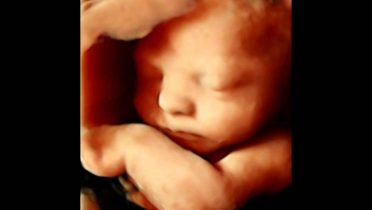

Las ecografías 5D son vídeos muy realistas en tiempo real construidos a través de imágenes tridimensionales que permiten ver de forma muy nítida la cara, expresiones, gestos y movimientos del feto. Son una prueba que aporta un gran valor emocional y sentimental a los padres puesto que pueden ver a su hijo en tiempo real y con una gran precisión antes de que nazca.

- Las 5D ofrecen vídeos con gran nitidez en tiempo real. Este tipo de ecografías ofrecen una tonalidad de sombras mucho más precisa y de matices que aumenta su realismo. Con este tipo de imágenes es posible distinguir los rasgos faciales del feto. Permiten ver con más nitidez posibles problemas en el feto, aportando luz en las zonas menos visibles y haciendo desaparecer obstáculos que impiden el análisis.